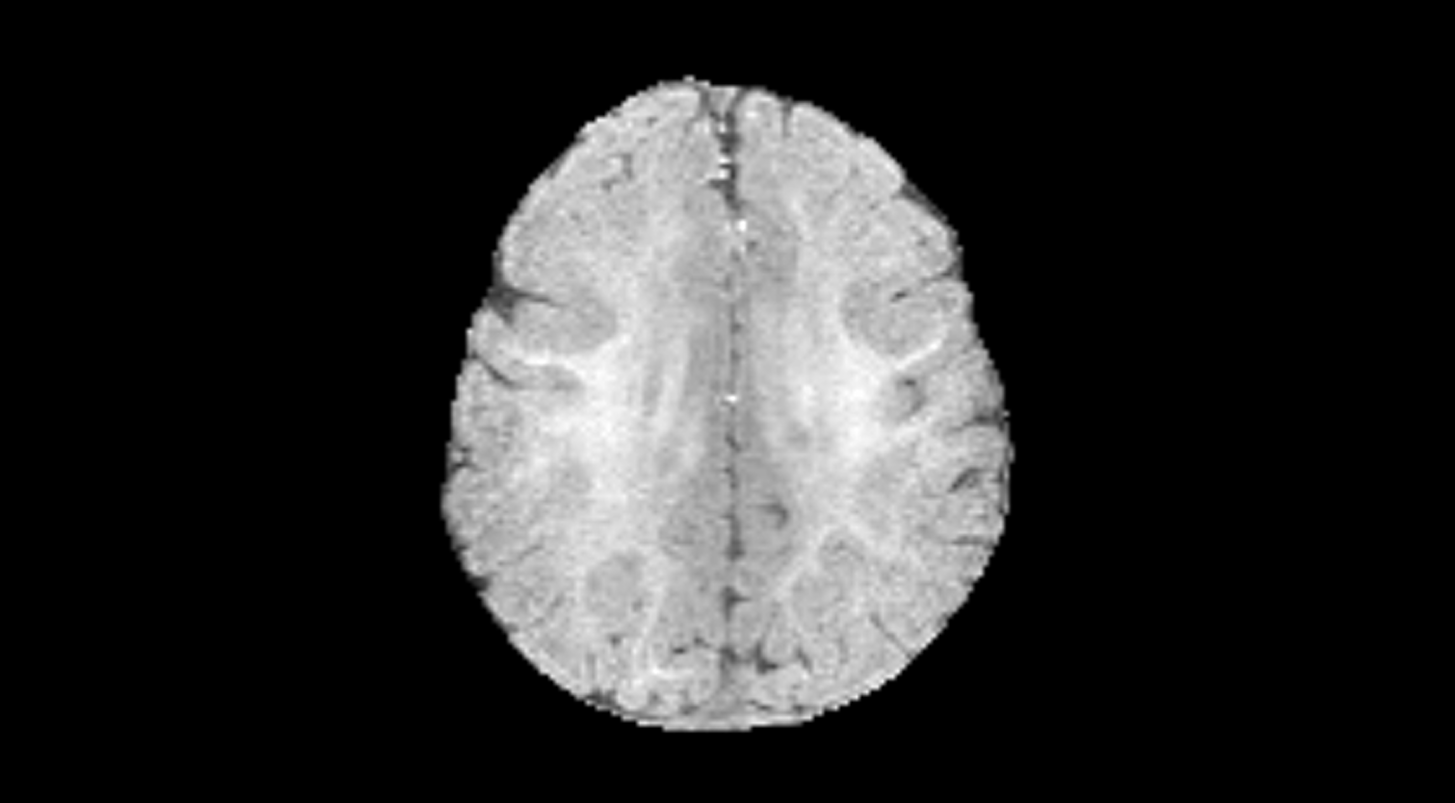

Вот как это работает на валидационной выборке. Исходное исследование из выборки:

Пример работы алгоритма: